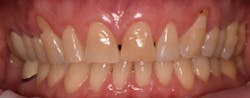

This new biological approach involving blood derivatives A-PRF and I-PRF combined with precision minimally invasive surgery for root coverage demonstrates faster healing without the need of a donor site. The morbidity of GDT is decreased and patient case acceptance is higher compared with traditional grafts. Before-and-after pictures are shown below (figures 15–22).